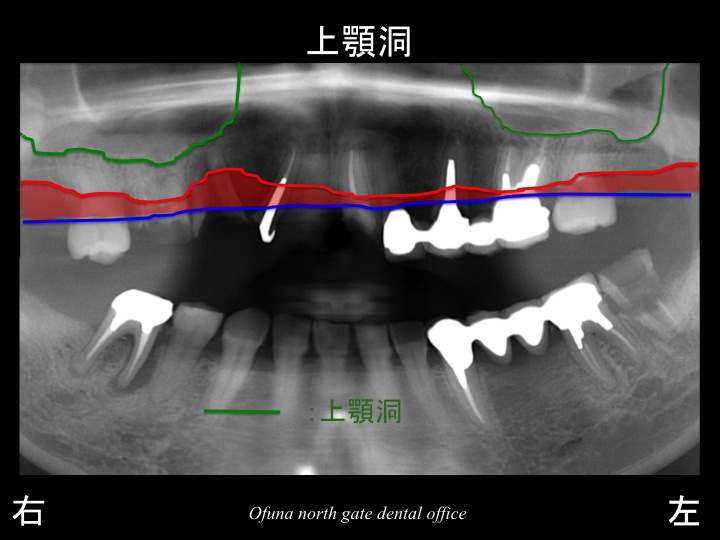

骨吸収の状態を線で書いたのが以下のレントゲンになります。

青線が骨吸収を起こす前の骨の位置です。

赤線は、現在の骨の位置です。

さらに分かりやすくするために 骨吸収部位を赤色の領域で表しします。

骨吸収が起こっているのが分かるかと思います。

さらに上顎の右側では、上顎洞 の存在が問題となっていました。

緑線は上顎洞という空洞です。

骨ではなく、穴が開いているのです。

これも さらに分かりやすくするために、上顎洞 緑色で表示します。

骨吸収と上顎洞 の存在により、上顎右側の奥歯では、インプラントを埋入するための骨の高さが十分に存在していません。